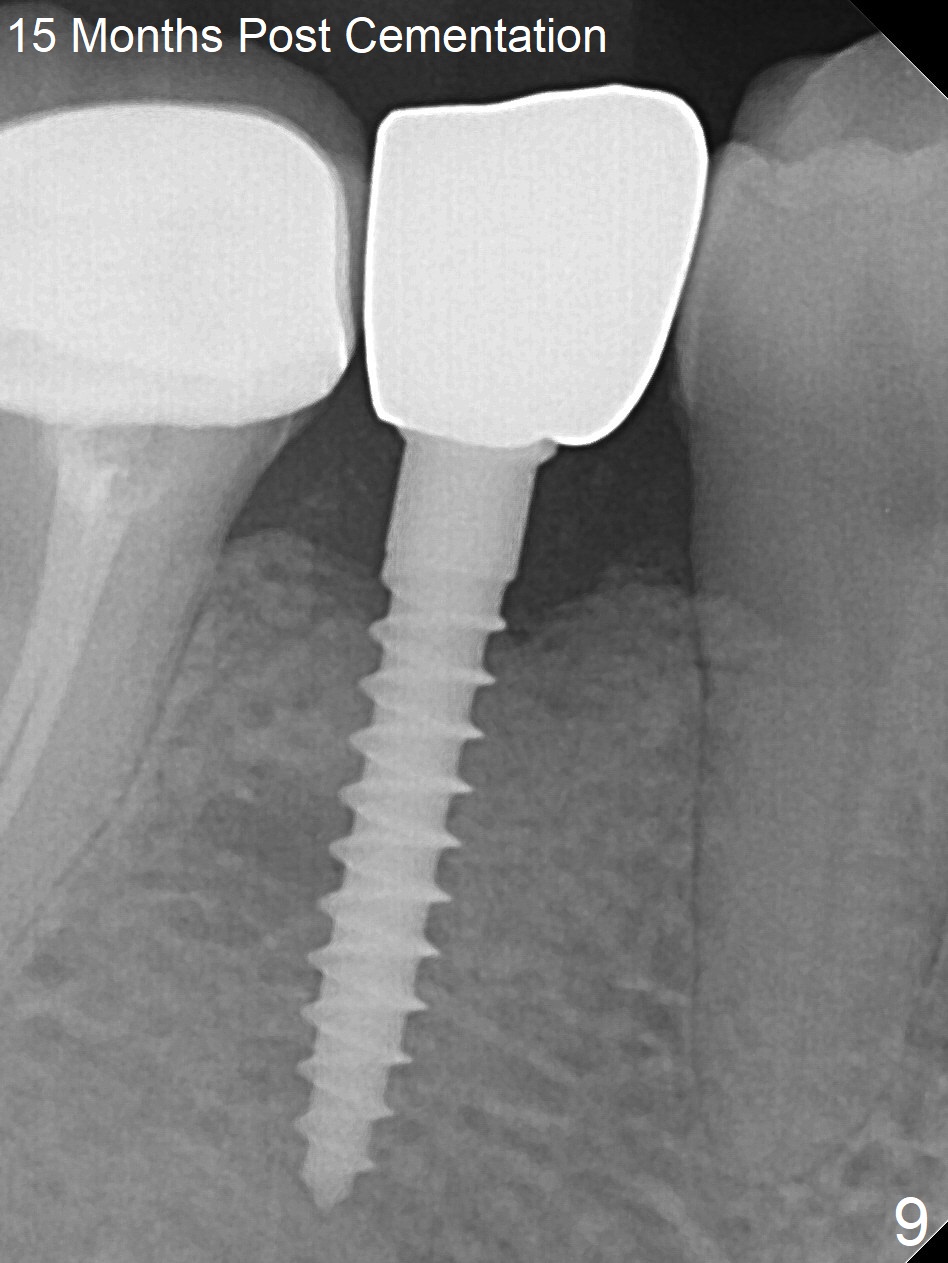

Preop photo shows the distal inclination of the tooth #28 (Fig.1).  The distal surface of the latter is reduced before incision for implant placement at #29 (Fig.2).  The buccolingual width is approximately 4 mm, as compared to 3 mm implant positioner (Fig.3).  After 1.2x10 mm osteotomy (Fig.5), the mesiodistal cortical bone is removed with a small high-speed fissural bur (Fig.4).  When a 2.5x12(2) mm 1-piece implant is placed (Fig.6), there is no buccal (Fig.7) or lingual plate perforation.  There is no postop paresthesia.  There is mild bone loss distal 4 months postop (Fig.8 *).  Take photos before and after permanent crown cementation to show increase in ridge width after bone graft and improvement in gingival health after provisional modification.  Take PA and/or BW post cementation to show that the distal bone resorption (Fig.8 *) is partially due to angulation.  No continuous bone loss 15 months post cementation (Fig.9).  There is mild bone resorption mesially 2 years 3 months post cementation (Fig.10).  The soft and hard tissues remain healthy 4 years 3 months post cementation (Fig.11,12).